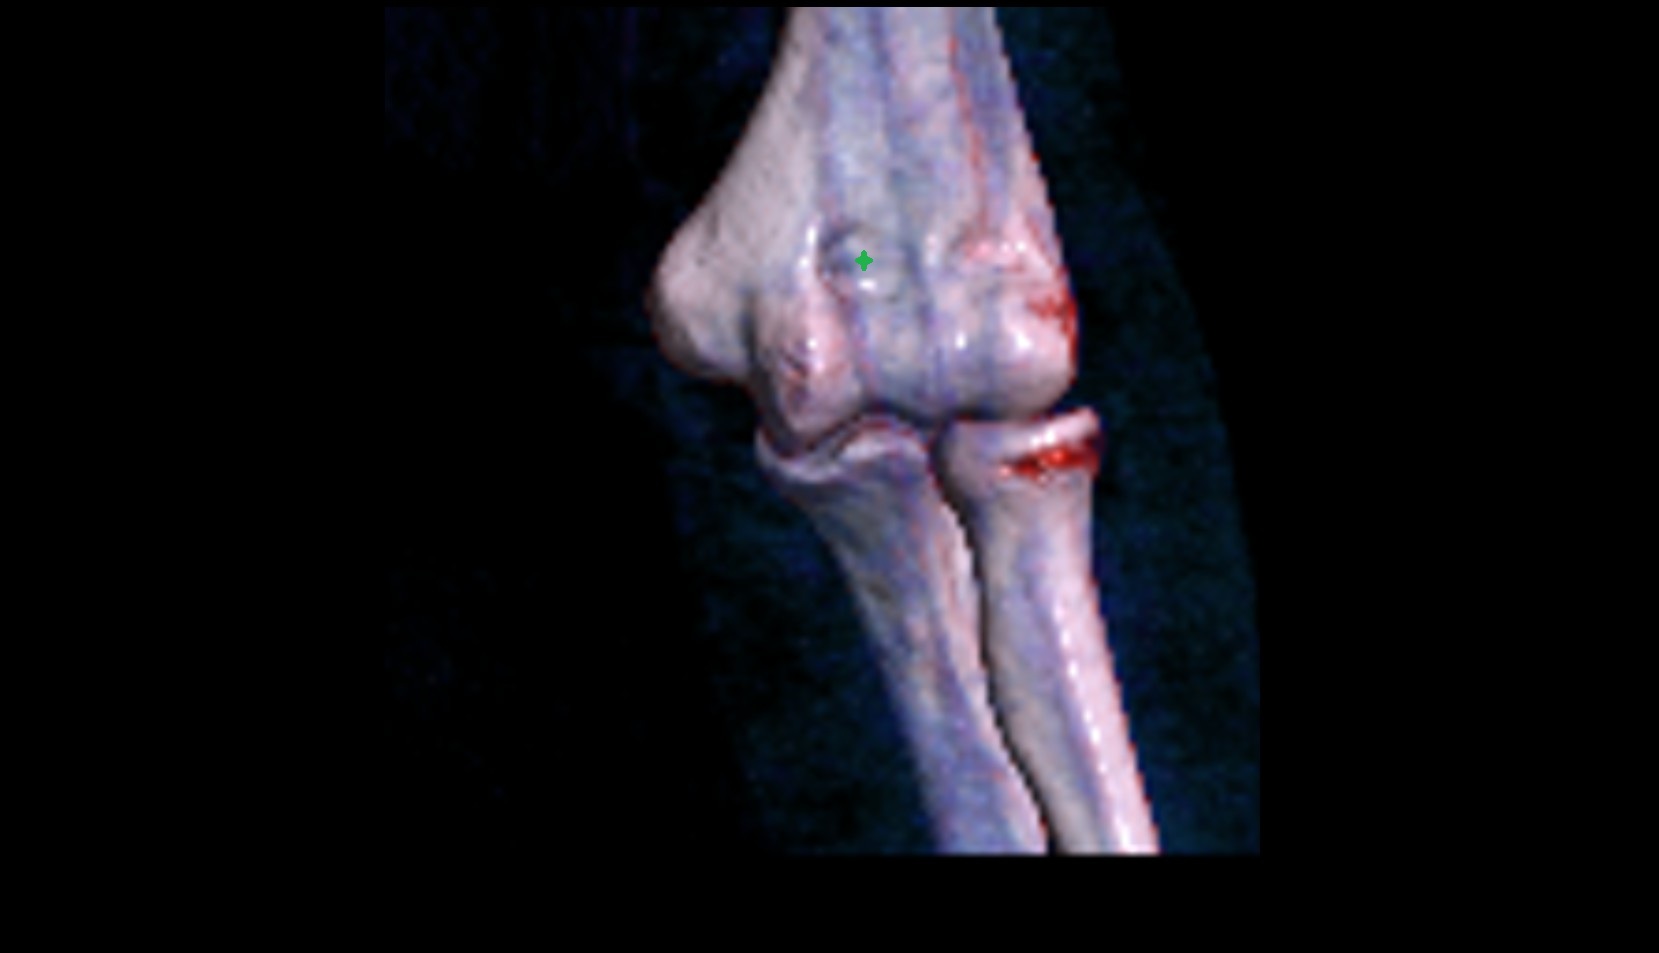

- Knee Joint